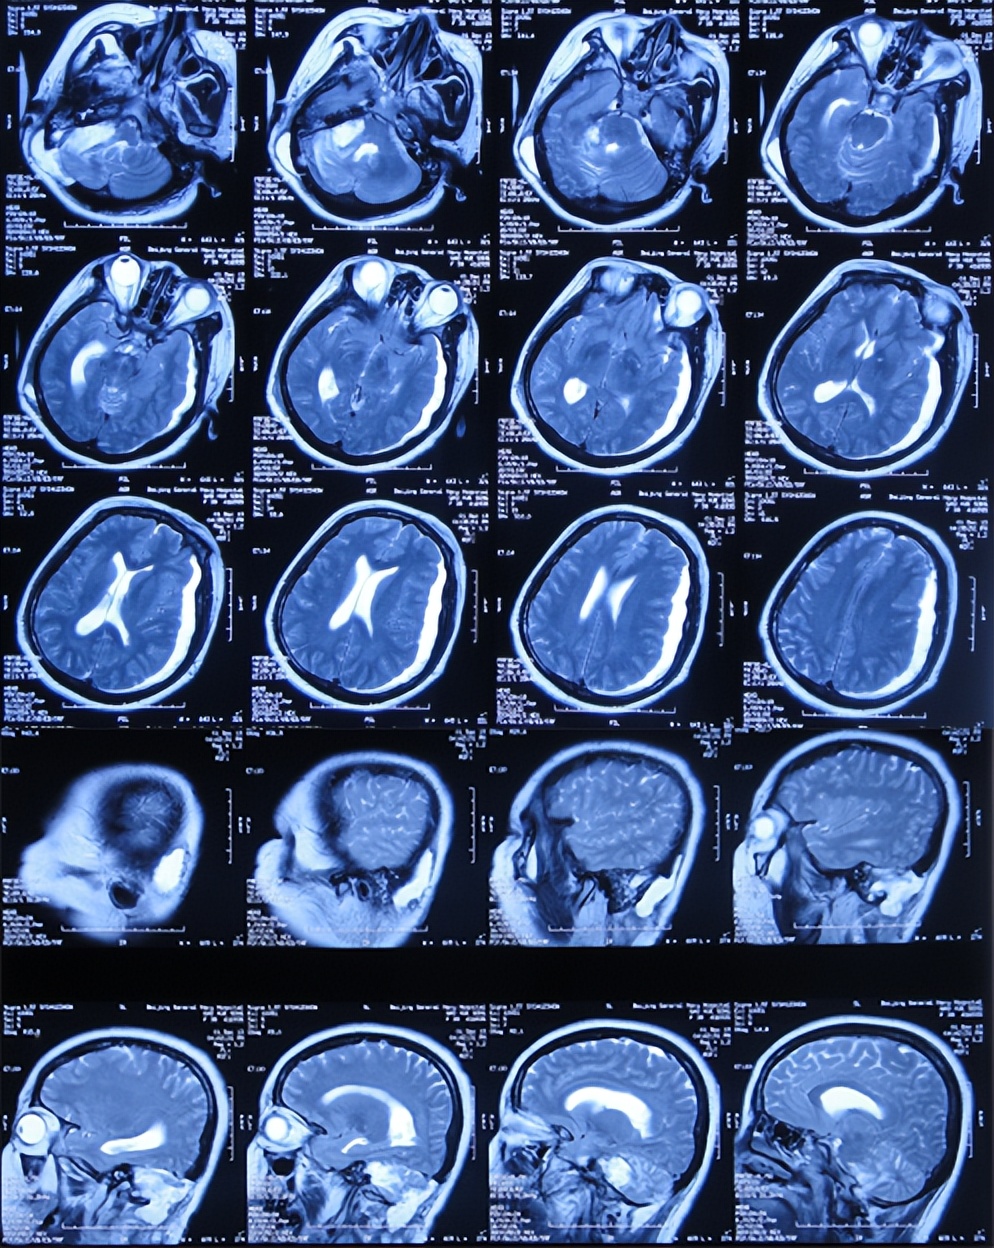

当天转至上级的山西省某省级三甲医院,查头颅核磁(图-2)示听神经瘤,需要手术。

图-2:2013年11月6日头颅核磁和核磁增强